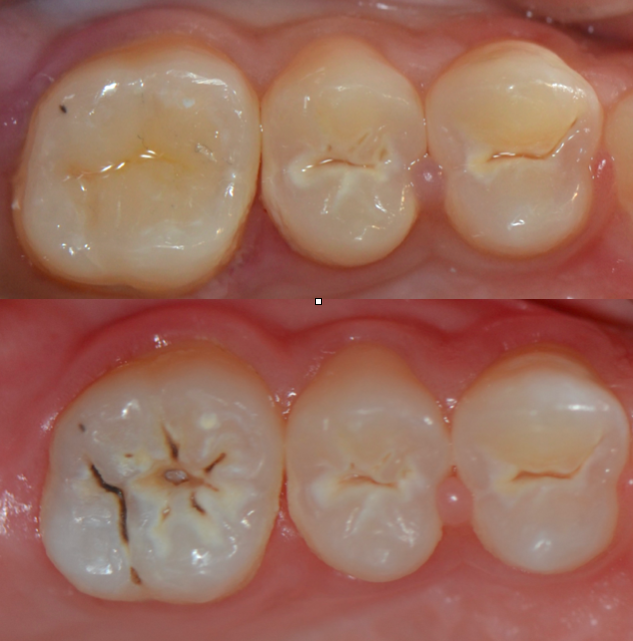

以往的博客大家對牙齒合面形態(tài)的堆塑普遍關(guān)注,除了掌握牙齒形態(tài),其實(shí)技巧不多,手法很重要。今天給大家分享一個(gè)病例,利用一些小技巧復(fù)制合面形態(tài)的重現(xiàn)。我個(gè)人還是喜歡分層堆塑的方法重新恢復(fù)形態(tài),第一次使用印章法多多關(guān)注。

適應(yīng)癥是合面已發(fā)生齲壞但尚未出現(xiàn)缺損的牙齒。

術(shù)后即刻照

20151112162536_64068.png

術(shù)前術(shù)后對比

20151112162632_45798.png